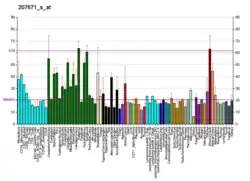

The bestrophin family of proteins comprises four evolutionary related genes (BEST1, BEST2, BEST3, and BEST4) that code for integral membrane proteins.[6] This family was first identified in humans by linking a BEST1 mutation with Best vitelliform macular dystrophy (BVMD).[7] Mutations in the BEST1 gene have been identified as the primary cause for at least five different degenerative retinal diseases.[7]

The bestrophins are an ancient family of structurally conserved proteins that have been identified in nearly every organism studied from bacteria to humans. In humans, they function as calcium-activated anion channels, each of which has a unique tissue distribution throughout the body. Specifically, the BEST1 gene on chromosome 11q13 encodes the Bestrophin-1 protein in humans whose expression is highest in the retina.[7]

Tissue and subcellular distribution

The location of expression of the BEST1 gene is essential for protein functioning and mislocalization is often connected to a variety of retinal degenerative diseases. The BEST1 gene expresses the Best1 protein primarily in the cytosol of the retinal pigment epithelium. The protein is typically contained in vesicles near the cellular membrane. There is also research to support that the Best1 protein is localized and produced in the endoplasmic reticulum (intracellular organelle involved in protein and lipid synthesis). Best1 is typically expressed with other proteins also synthesized in the endoplasmic reticulum, such as calreticulin, calnexin and Stim-1. Calcium ion involvement in the countertransport of chloride ions also supports the idea that Best1 is involved in forming calcium stores within the cell.[10]